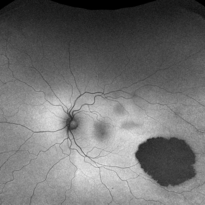

Congenital Hypertrophy of the Retinal Pigment Epithelium Autofluorescence Optomap

Sep 24 2019 by Sophia El Hamichi, MD

A 52-year-old female followed for 2 temporal lesions of CHRPE OD and white without pressure.

Photographer: Sophia El Hamichi, MD, Murray Ocular Oncology and Retina, Miami

Condition/keywords: autofluorescence imaging, congenital hypertrophy of the retinal pigment epithelium (CHRPE), Optomap, ultra-wide field imaging, white without pressure